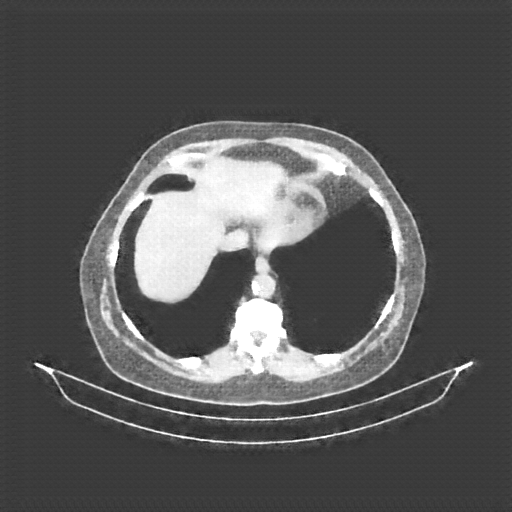

Original NATIVE CT scan (input)

Full window (WL 1023.5, WW 4095 β†’ Low βˆ’1024, High +3071)

Actual HU range: [-160.0, 240.0]